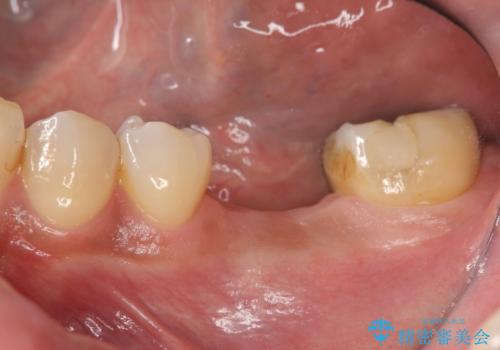

[ 歯槽堤保存術 ] [ 奥歯の破折 ] ソケットプリザベーションを併用したインプラント治療